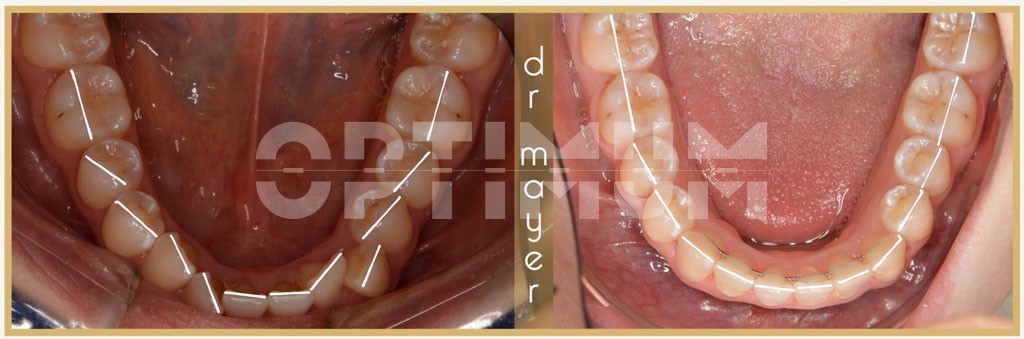

Páciensünk esztétikai fogszabályozás céljából kereste fel az OPTIMUM Fogászatot. Szájvizsgálat után a beszűkült alsó és felső fogívek miatt kialakult súlyos torlódást találtunk. A beszűkült fogívek miatt mosolygáskor kevés fog látszódott. A felső szemfogak teljesen kiszorultak a sorból. A fogívek előnytelen V alakúak voltak, mely miatt a felső metszőfogak előre állónak tűntek. Az oldalsó koponyaröntgen vizsgálata alátámasztotta, hogy a felső metszőfogak pozíciója arcesztétikai szempontokból is megfelelő.

Az egyértelmű volt, hogy alsó/felső rögzített fogszabályozó készülékre van szükségünk az megfelelő eredmény eléréséhez. Foghúzás évekkel ezelőtt szóba jöhetett volna, de ma már nem csak szabályos fogakat, hanem gyönyörű mosolyt is szeretnék pácienseimnek adni. Így szóba sem kerülhetett ép fogak eltávolítása. Lágyerővel működő, önligírozó, rögzített H4 készülék mellett döntöttünk. A modern kezelési elveknek és anyagoknak hála sikerült a fogíveket megtágítani és szép U alakú íveket kialakítani. Harapásemelők segítségével biztosítottuk, hogy könnyen és gyorsan tudjuk a fogíveket tágítani.

A kezelés közben gumihúzásokkal folyamatosan szükséges volt kontrollálni a harapási magasságot, hogy ne alakuljon ki nyitottharapás. Így sikerült elérni, hogy mosolygáskor szép mosoly ívet kapjunk és a fogak kitöltsék a mosolyt!